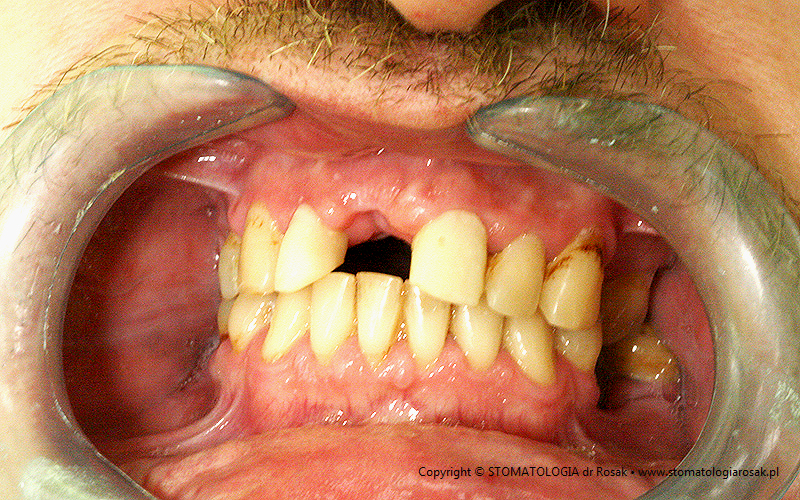

7. Pacjent lat 47 z utraconą jedynką górną.

| 7a. Stan przed leczeniem |